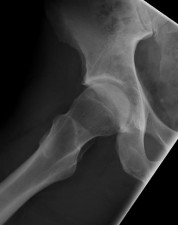

ORTHOPEDIC MCQS BANK OITE 96 96.1 A 4‑year‑old girl has had increasing left hip pain over the past 48 hours a…